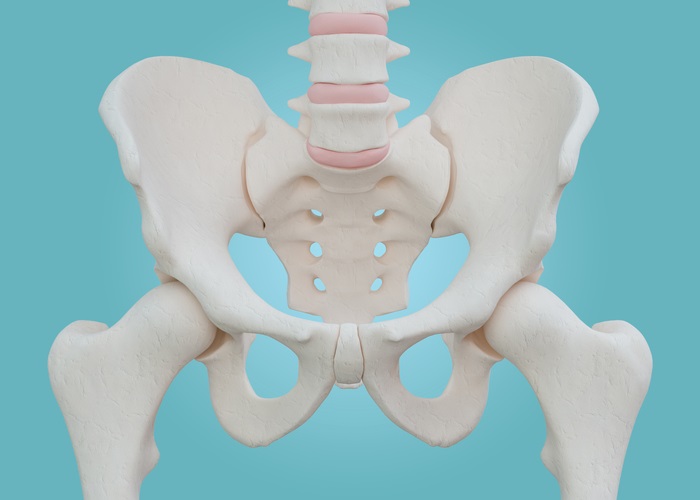

재활 훈련

수술 후 2주 정도 지나면 본격적인 재활 훈련이 시작됩니다. 물리 치료사와의 상담하에 맞춤형 프로그램이 운영되며, 이 과정에서 주요 목표는 관절의 가동 범위를 회복하고, 근력을 강화하는 것입니다.

- 가동 범위 운동: 고관절의 유연성을 회복하기 위한 다양한 운동이 필요합니다. 초기에는 간단한 스트레칭부터 시작하여 점차 난이도를 높여가야 합니다.

- 근력 훈련: 다리와 엉덩이의 근력을 강화시키기 위한 다양한 운동이 필요합니다. 이를 통해 일상적인 움직임을 회복할 수 있습니다.

- 균형 훈련: 넘어지는 것을 방지하기 위한 균형 훈련도 중요한 부분입니다. 스탠드와 같은 기구를 이용하여 반복적인 연습이 필요합니다.

재활 훈련은 반드시 전문가와 함께해야 하며, 각 개인의 상황에 맞춰 조정되어야 합니다. 이 단계에서 규칙적인 운동이 이루어지지 않으면 회복이 지연될 수 있습니다.

완전 회복 단계

수술 후 약 6주가 경과하면 상당한 회복이 이루어집니다. 이 단계에서는 보다 일상적인 활동을 재개할 수 있으며, 대부분의 환자가 독립적으로 걷고 일상 생활을 할 수 있는 능력을 회복하게 됩니다.

- 운동 재개: 통증이 줄어들고 일상 생활이 가능해짐에 따라 더 많은 활동을 시작할 수 있습니다. 하지만 지나치게 무리하지 않도록 각별한 주의가 필요합니다.

- 체중 부하: 체중 부하를 점차적으로 증가시켜야 합니다. 처음에는 크러치나 보행기 등을 사용하고, 점차적으로 홀로 걷는 연습을 합니다.

- 사회적 활동: 사회적 활동 참여를 늘려가는 것도 중요한 요소입니다. 전반적인 심리적 안정성이 회복되는 데 도움이 됩니다.

이 단계에서의 체계적인 관리를 통해 최종적인 삶의 질 향상을 도모할 수 있습니다. 완전 회복 단계에서 환자는 수술 전보다 더 높은 수준의 활동성을 가질 수 있습니다.